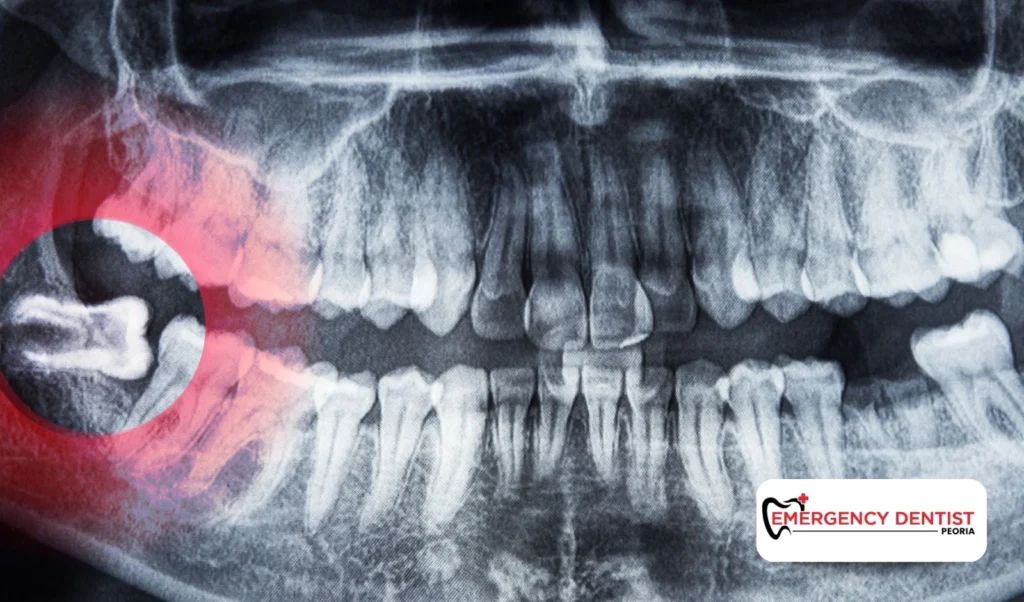

If you are searching for how to get accurate wisdom tooth removal costs, scheduling an exam is the best first step. X-rays allow the dentist to determine tooth position and the correct extraction approach.

An impacted wisdom tooth does not fully break through the gums. This can lead to pressure, swelling, or infection. Removing impacted teeth often requires oral surgery techniques and careful planning.

Because of the added steps involved, impacted cases often influence the average cost of a wisdom tooth removal more than straightforward extractions.